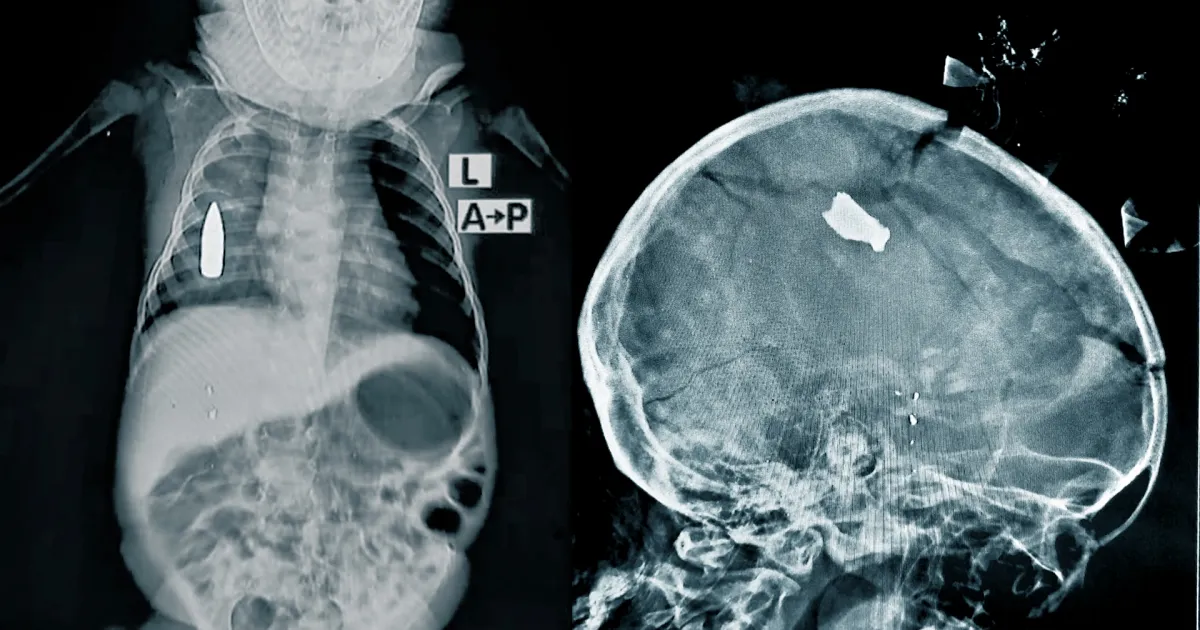

Röntgenbilder zeigen schwere Verletzungen bei Kindern: eine Kugel im Körper des 18 Monate alten Jungen und einen Granatsplitter im Kopf des 20 Monate alten Mädchens.

Ende Oktober wurden nach einer Explosion auf einem Markt mehr als 30 Verletzte ins Bashair-Krankenhaus eingeliefert, darunter zwölf Kinder unter 15 Jahren. Sie litten an schweren Verbrennungen und anderen Verletzungen. Ein 20 Monate altes Mädchen hatte einen Granatsplitter tief im Kopf stecken. „Als wir sie vorsichtig auf den Röntgentisch legten, fiel ein Teil der zerbrechlichen Schädeldecke auf den Tisch“, schildert Dr. Moeen*. „Zum Glück überlebte sie – aber vielen anderen können wir nicht mehr helfen.“